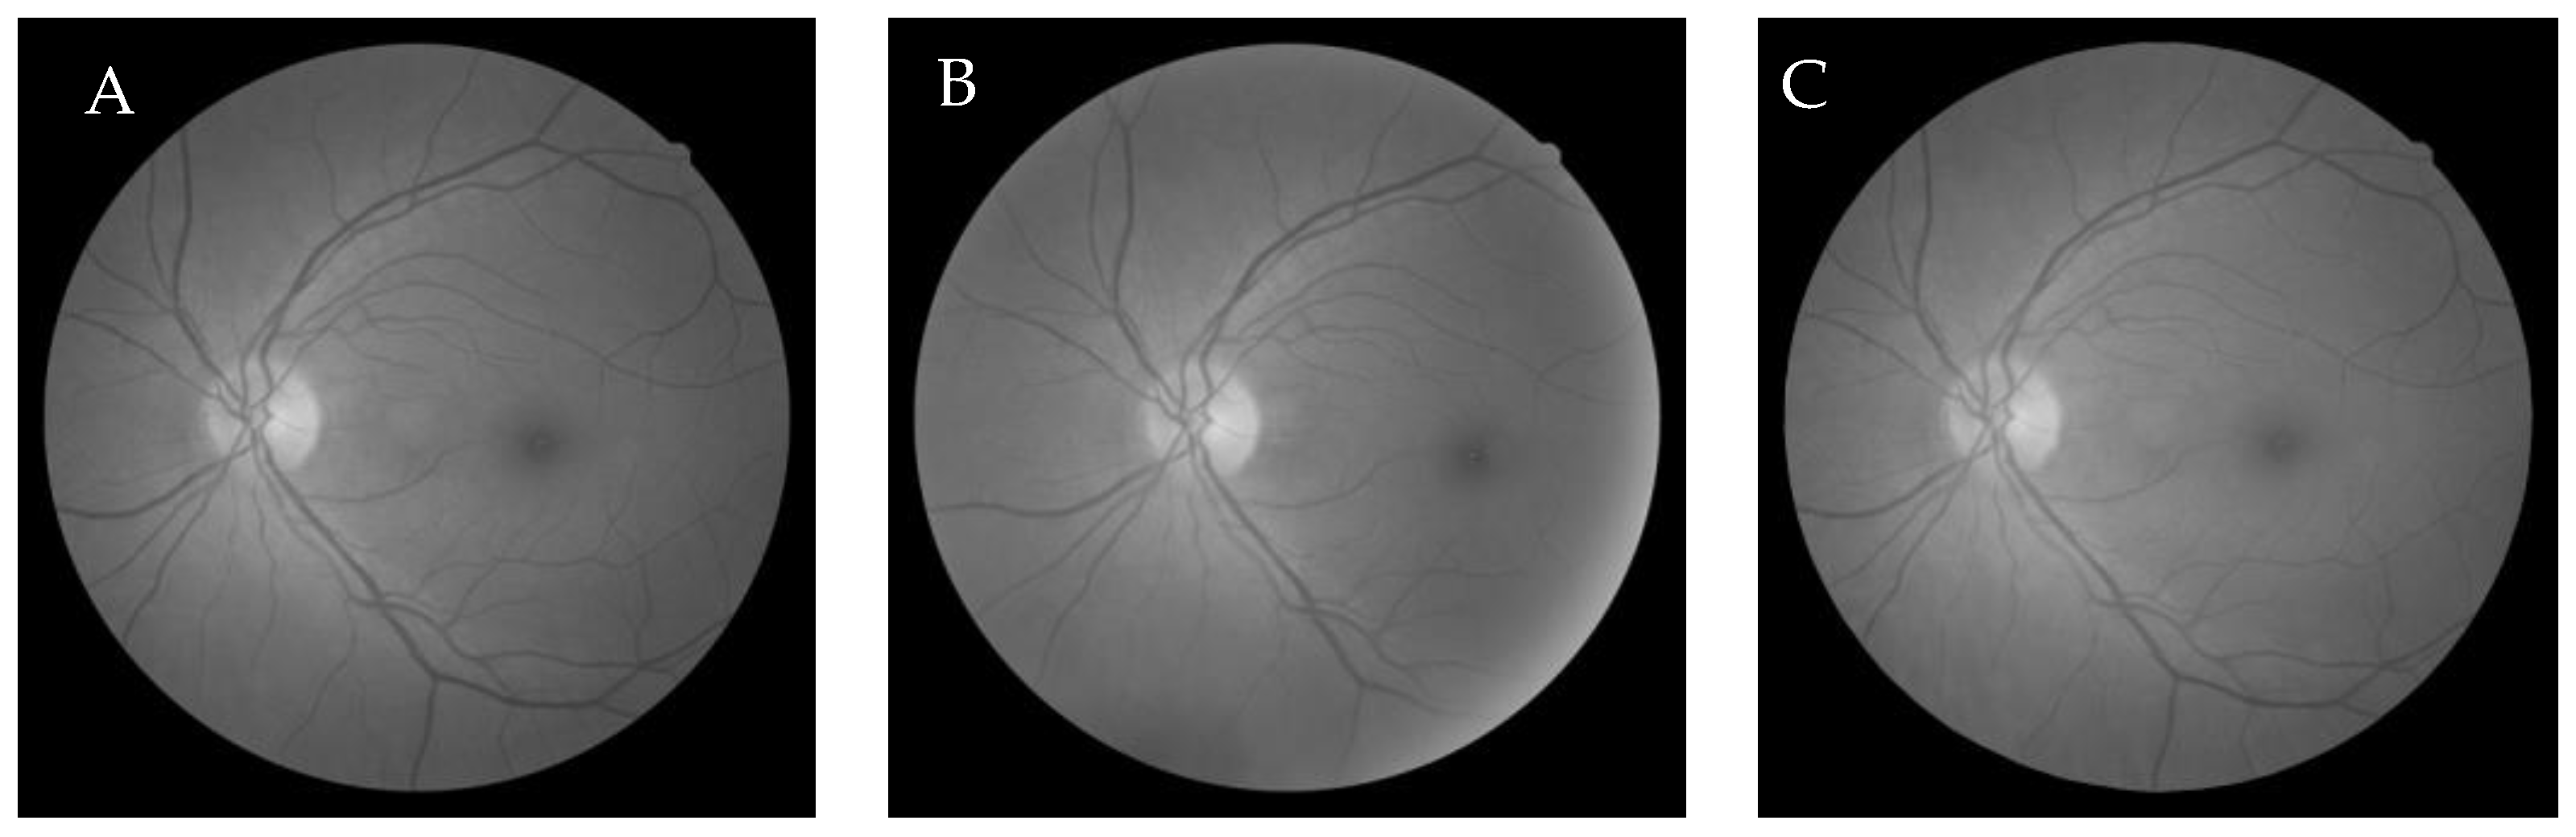

6.2.1. Grey-Wolf Optimization-Based Wang’s Demons Registration